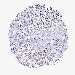

CANCER BREAST CANCER Show tissue menu

BRCA TCGA BRCA VALIDATION PROTEIN EXPRESSION

Breast cancer

Human cancer